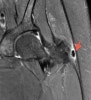

- MRI

석회화 건염의 진단을 위해 시행하는 경우는 드물지만, 감염, 골절이나 종양성 질환과의 감별을 위해 시행하기도 합니다.

대개 T2 강조 영상에서 주변 연부 조직의 신호 증가 소견이 관찰되고, 골수 부종 소견이 관찰되기도 합니다.

MRI : 고관절 주위 석회화 건염(Calcific tendinitis around the hip)